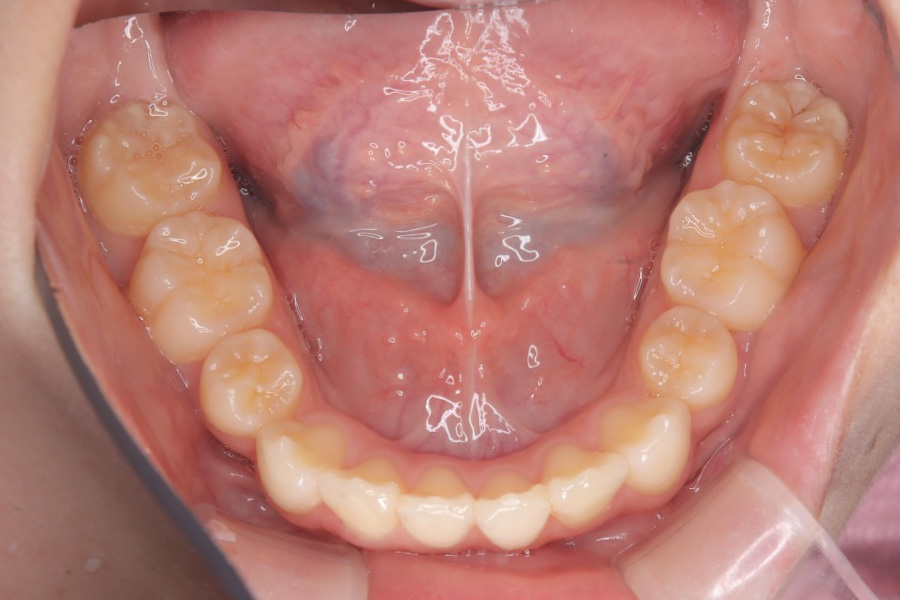

治療後

主訴 歯のスペースを閉じたい

期間 2年

治療内容 インビザライン矯正

非抜歯

治療に伴うリスク 矯正終了後は、リテーナーを指示通りに使用し、歯の後戻りを防ぐ必要があります。